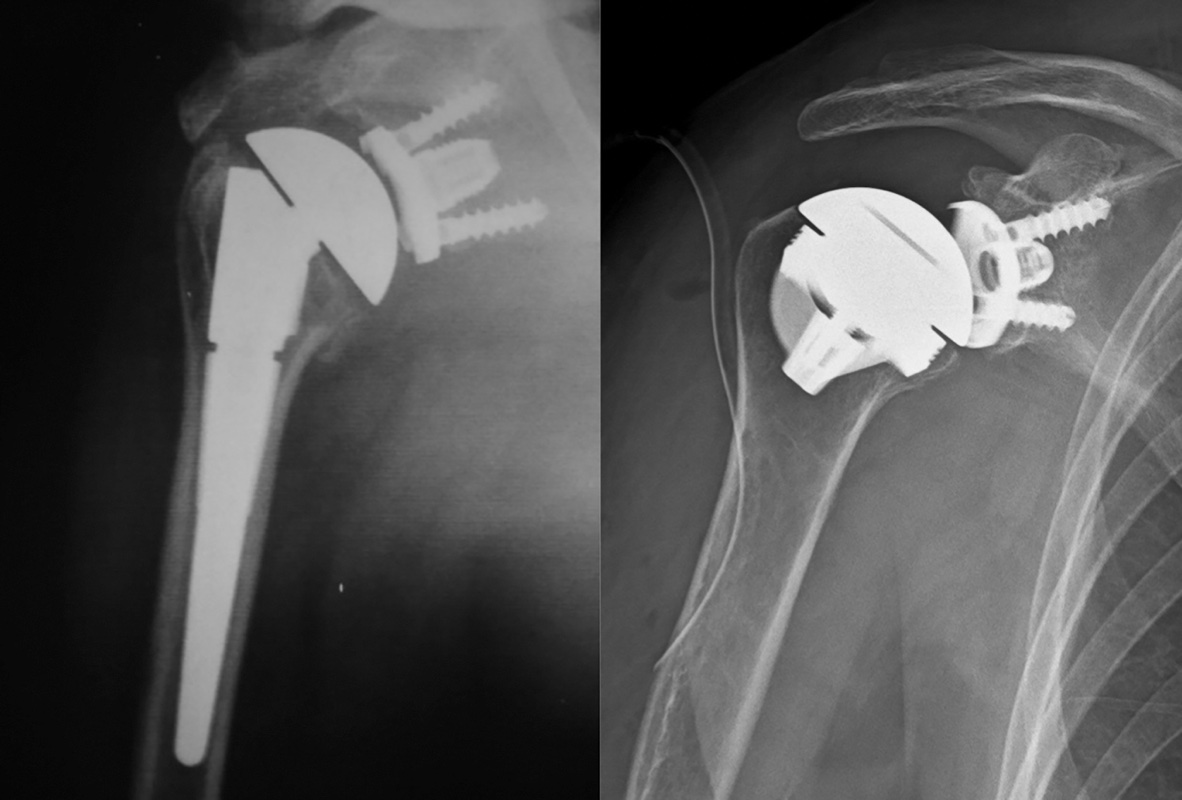

Lo stesso risultato può essere raggiungibile lateralizzando la glenosfera. Ciò può essere ottenuto o interponendo tra superficie articolare e metal back un tassello osseo prelevato o dalla testa omerale asportata o dalla cresta iliaca (BIO reverse)10 (Fig. 3), oppure creando un ulteriore spessore metallico.

Sorprendentemente, il tentativo di eliminare il fenomeno dello scapular notching ha portato a un inatteso incremento della mobilità post-operatoria. Un ulteriore incremento della mobilità può anche essere ottenuto impiantando glenosfere più grandi; tuttavia l’aumento delle dimensioni della glenosfera riduce lo spazio operatorio e rende particolarmente indaginosi alcuni passaggi tecnici.